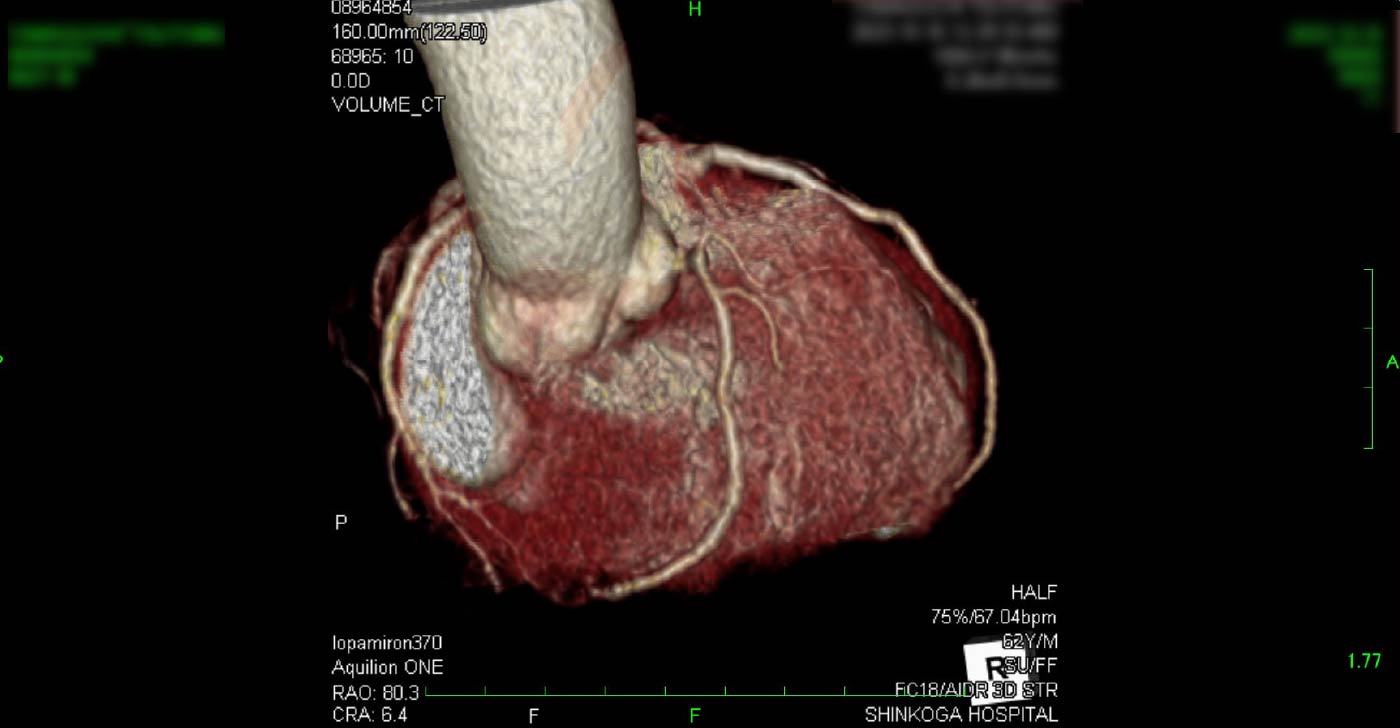

進行期 造影心臓CT 重症心筋虚血症例

冠動脈CT

狭心症を安全に診断あるいは除外する!

連携施設の新古賀病院で速やかに実行可能です。

冠動脈CT 冠動脈CT 冠動脈CT 冠動脈CT 冠動脈CT 冠動脈CT 冠動脈CT 冠動脈CT 冠動脈CT 冠動脈CT 冠動脈CT 冠動脈CT 冠動脈CT 冠動脈CT